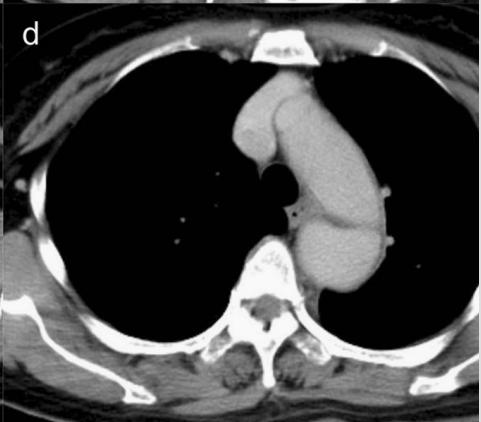

下图的胸部CT平扫,基本上大约肯定可以看到一条线样阴影,将主动脉一分为二!

图10

增强CT一看,主动脉裂开了!

图11